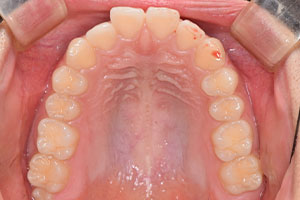

치료증례 전후사진

Before & After